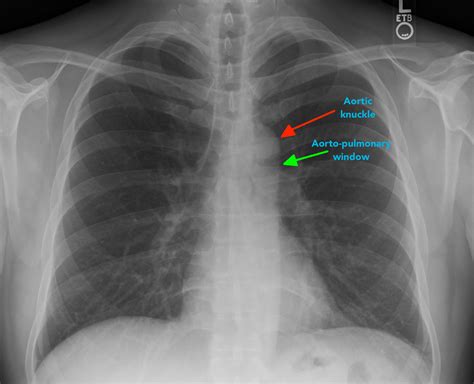

• Heart: Assess the size and shape of the heart. Look for any enlargement or abnormal contours.

• Mediastinum: Check for any widening or masses in the mediastinum, the central compartment of the chest.